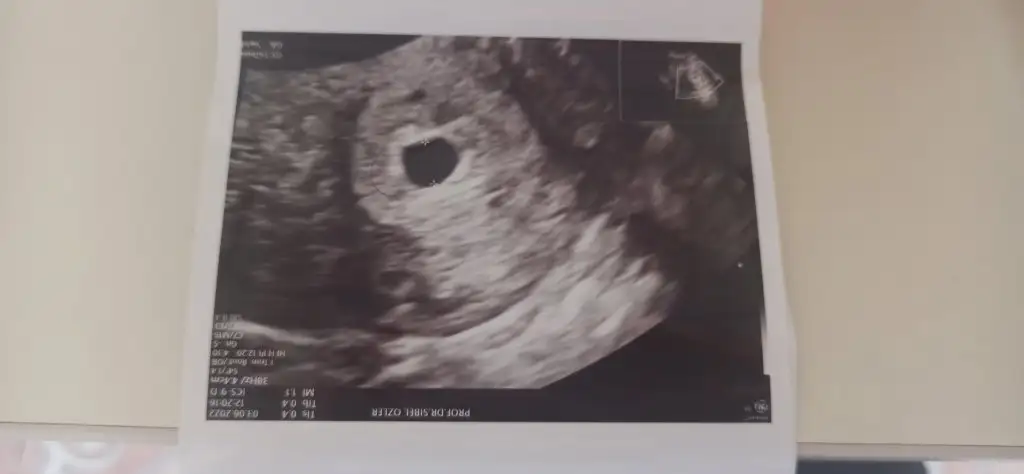

Merhaba sad 22 Nisan 6+3 hamileyim geçtiğimiz cuma kontrole gittim HCG 1871,77 kese gözüktü ama haftasına göre küçük dedi doktor bebek de gözükmedi boş gebelik mi? Ne yapmalıyım?

Bazen geç döllenme olabiliyor canım inşallah sağlıkla güzel ilerler gebeliğinMerhaba benim de son adet tarihim 15 Nisan yani bebek 7+3 olması gerekirken bugün 5 haftalık çıktı ultrasonda. Bebeği zoraki gördük minicik kalp atışını duyamadık. Geç döllenme deniyor normal bir durum.